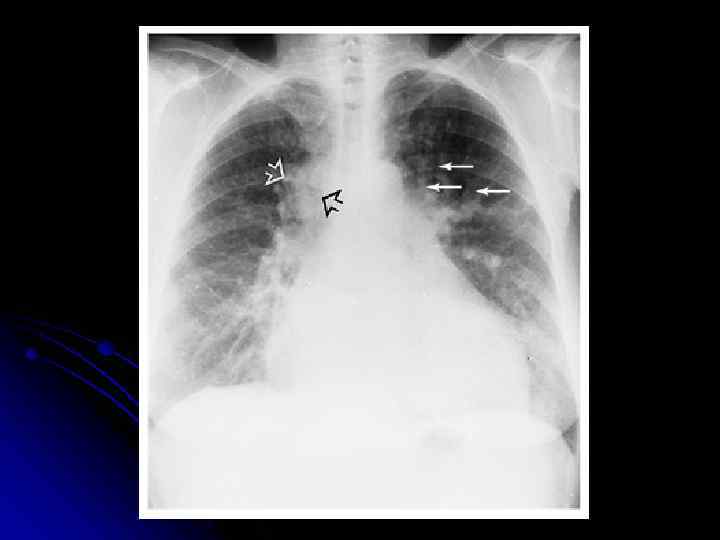

Рентгенография l l l Сосуды в верхних долях крупнее, чем в нижних (перераспределение легочного рисунка) давление в ЛП 15 -20 мм рт. ст Признаки интерстициального отека легких (Влинии Керли, признаки периваскулярного и субплевральныго отека) - давление в ЛП 20 -25 мм рт. ст. Признаки альвеолярного отека легких – затемнение легочных полей (симптом “бабочки”) давление в ЛП более 25 мм рт. ст. Размеры и форма сердечной тени Кардиомегалия – КТИ > 55 % Плевральный выпот (чаще при бивентрикулярной СН)

Рентгенография при СН